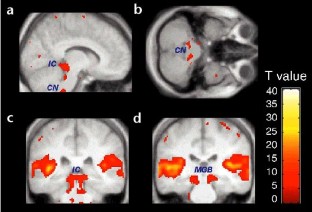

We measured the neural activity associated with the temporal structure of sound in the human auditory pathway from cochlear nucleus to cortex. The temporal structure includes regularities at the millisecond level and pitch sequences at the hundreds-of-milliseconds level. Functional magnetic resonance imaging (fMRI) of the whole brain with cardiac triggering allowed simultaneous observation of activity in the brainstem, thalamus and cerebrum. This work shows that the process of recoding temporal patterns into a more stable form begins as early as the cochlear nucleus and continues up to auditory cortex.

Griffiths, T., Uppenkamp, S., Johnsrude, I. et al. Encoding of the temporal regularity of sound in the human brainstem. Nat Neurosci 4, 633–637 (2001). https://doi.org/10.1038/88459